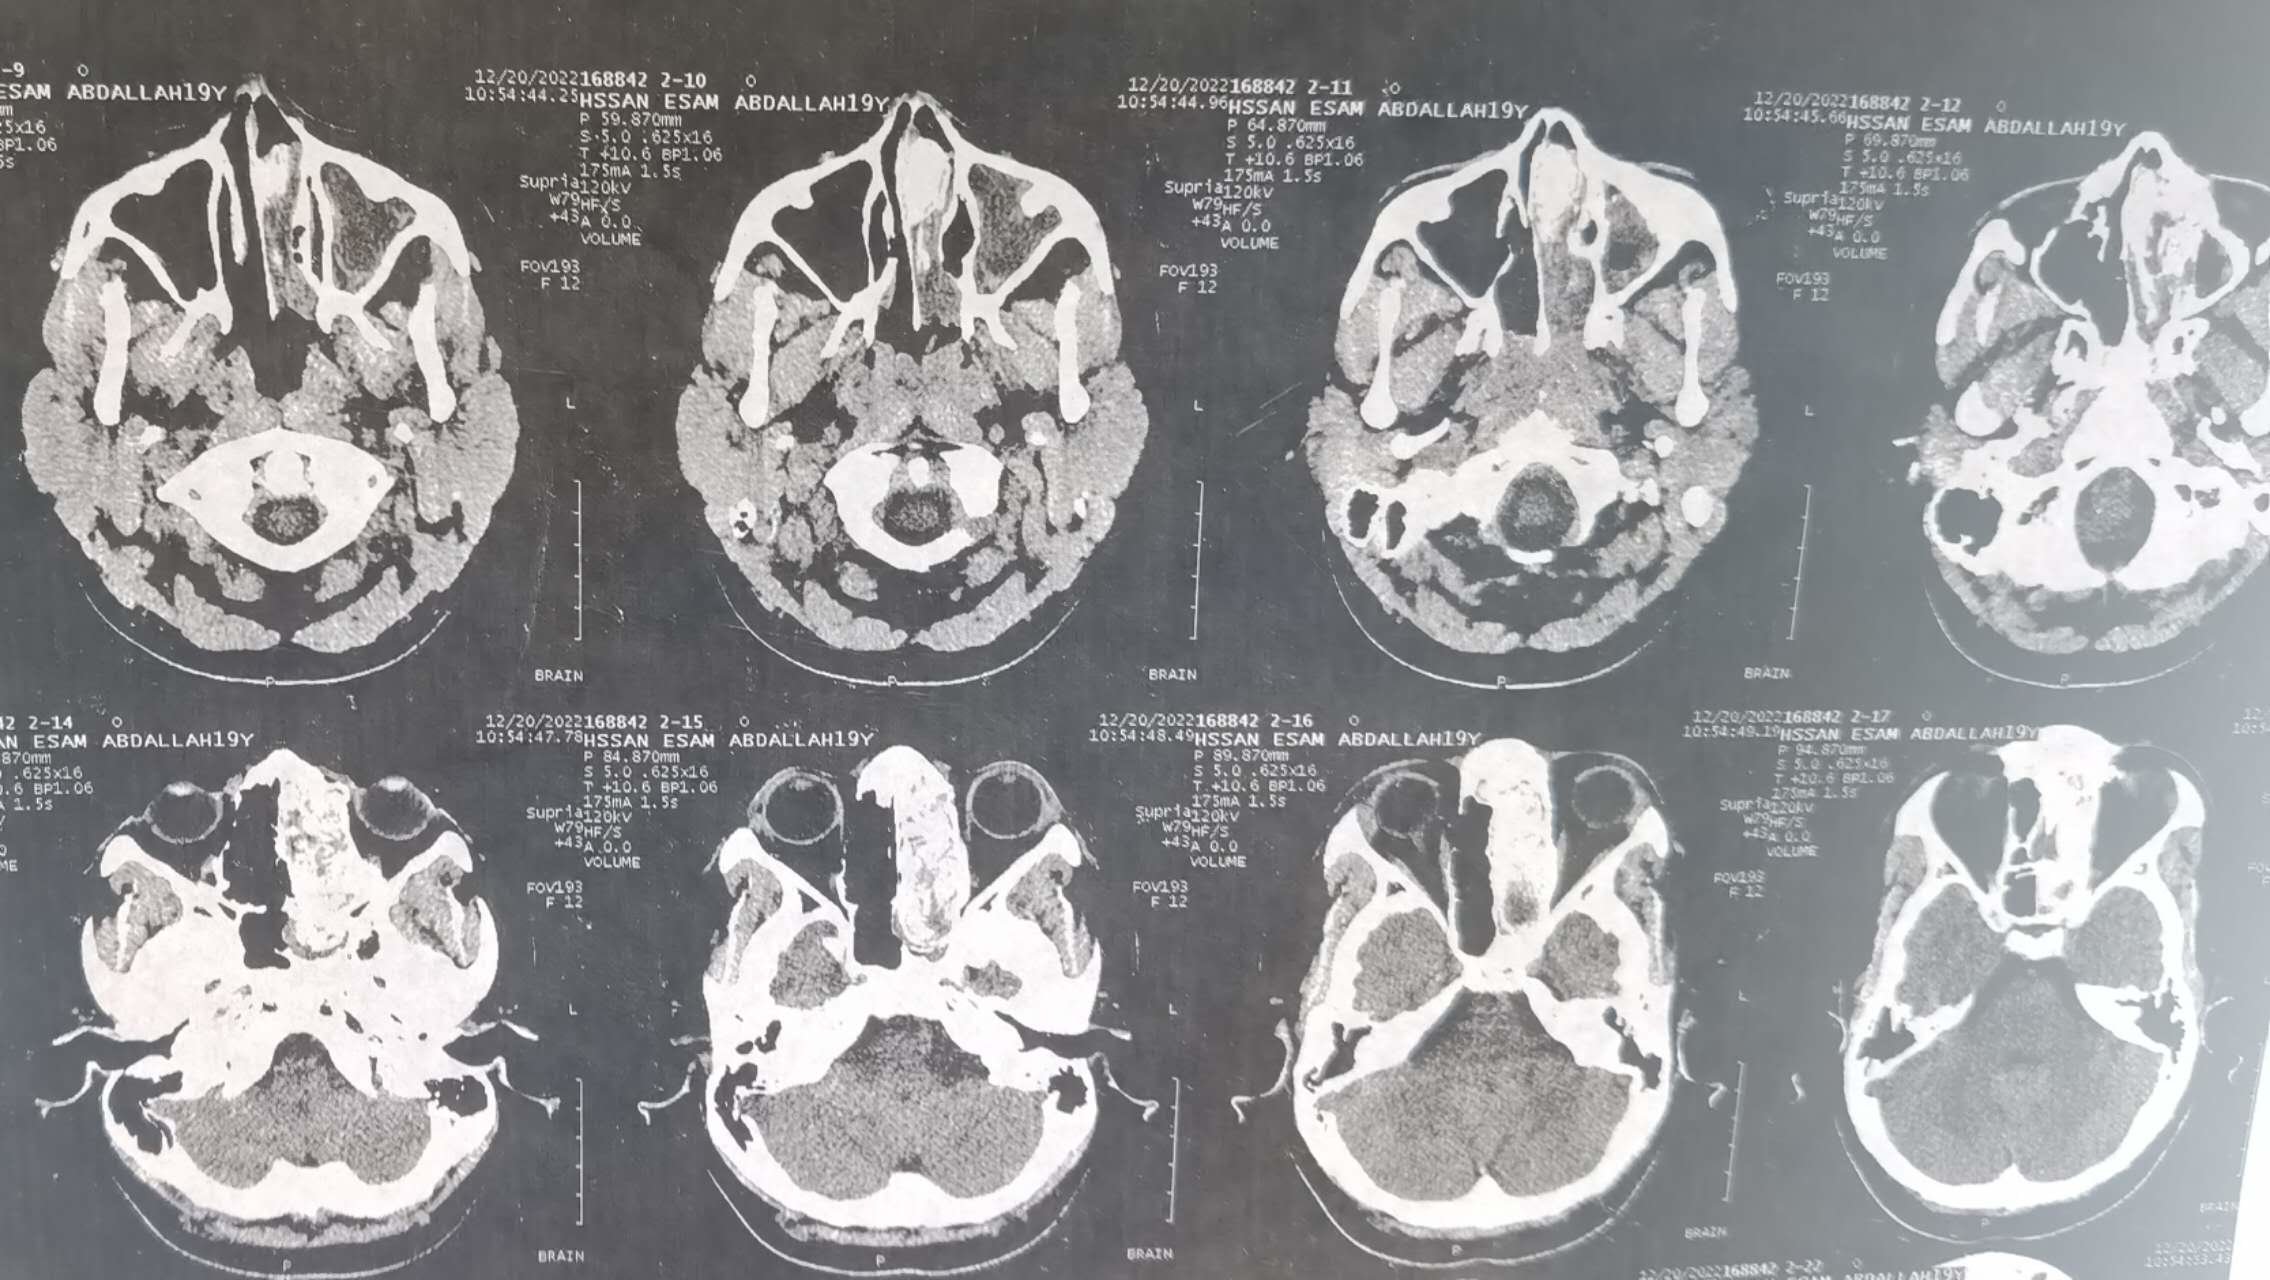

三周前的一个上午,援苏丹中国医疗队高天喜医生像平时一样按时上门诊开始诊疗工作,一个苏丹少年在家属陪同下走进诊室,咳嗽不止。陪诊家属代诉,患者15岁,间断咽痛,反复咳嗽5年。查体显示该患者双侧扁桃体重度肥大,左侧鼻腔巨大新生物,压迫鼻中隔偏至对侧鼻腔,双侧鼻腔无通气,张口呼吸。遂行血常规检查及鼻腔鼻窦CT检查,检查结果提示血常规无炎症表象,左侧鼻腔及巨大占位病变。

这名患者的症状及影像学检查显示鼻腔肿物大概率为良性,高天喜医生据此制定了治疗方案,术前予以口服抗生素一周,待控制炎症后全麻下一期行扁桃体及鼻腔鼻窦肿物切除术。被告知具体手术方案时,少年两眼放光,激动地伸出大拇指:“中国医生很好,能同时切除扁桃体及鼻腔肿物!”。后来助理据助理讲到,这名患者一度已经对治好鼻子不抱希望。

在助理密切配合下,这台术中鼻内镜突发故障的鼻腔肿物切除术最终顺利完成。如术前判断,鼻腔肿物良性,为中鼻甲异常气化的泡型结构伴有筛窦区真菌感染。气化的中鼻甲不足为奇,但是如此大体积的结构变异伴有真菌感染实属罕见。